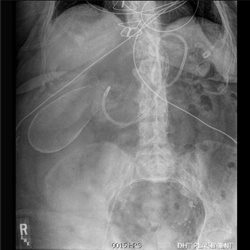

Abdominal: Plain Film 3

Various abdominal cases